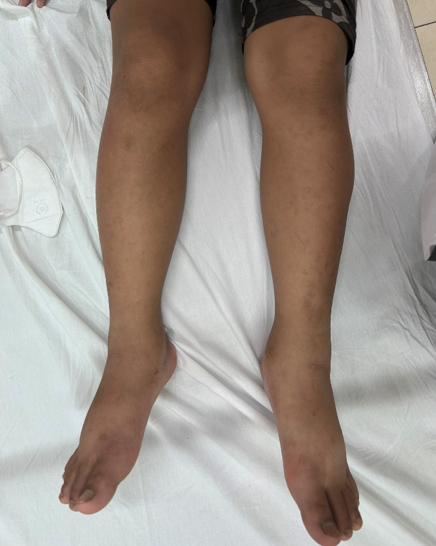

Trẻ nam, 12 tuổi địa chỉ A Lưới vào viện vì phù hai chi dưới. Khởi bệnh 2 tuần trước khi vào viện với phù 2 bàn chân và lan dần lên bắp chân, phù tăng từ từ, phù mềm, ấn lõm, Godet dương tính, đối xứng 2 bên kèm cảm giác râm ran như kiến bò và nặng ở bắp chân, đi lại nhanh mỏi và đi được đoạn đường ngắn. Ngoài ra người nhà nhận thấy trẻ mệt mỏi, không tham gia hoạt động vui chơi như trước đây, học bài không tập trung. Bệnh nhân được người nhà đem đi khám tại Bệnh viện Trường Đại học Y Dược Huế.

Nhập viện tại Khoa Nhi tổng hợp. Thăm khám các chỉ số sinh tồn: nhiệt độ 37°C; huyết áp 110/70 mmHg; mạch 90 lần/phút, cân nặng 46 kg, chiều cao 136 cm, BMI 21,4 kg/m2 (tăng 07 kg trong vòng 02 tuần), phù 2 cẳng và bàn chân, cảm giác râm ran như kiến bò và nặng ở bắp chân, đi lại được nhưng hạn chế, giảm trương lực cơ nhẹ, không thấy tổn thương các khớp. Khai khác thêm thông tin về hoàn cảnh, vì mất mùa sau đợt lũ lụt, sạt lở kéo dài nên gia đình không có đủ lượng gạo để sử dụng, nguồn lương thực chủ yếu phụ thuộc vào lượng gạo viện trợ, chủ yếu thay thế bằng các loại củ, rau rừng và cá khô. Đáng chú ý hơn là chế độ ăn của gia đình và trẻ là không ăn thịt từ nhỏ, hầu như chỉ ăn được các loại cá khô và không đa dạng các loại thực phẩm. Trẻ được khám lâm sàng, chỉ định xét nghiệm (VS, CKMB, Albumin máu, Protein máu, AST, ALT, Tổng phân tích nước tiểu, Protein niệu, Creatinin nước tiểu, Điện giải đồ, TSH, FT4, LH, FSH, testosterol, cortisol, Siêu âm bụng) để sàng lọc nhằm loại trừ các bệnh lý suy tim, thận, gan, nội tiết, chúng tôi nghi ngờ bệnh lý Beriberi trên trẻ. Trẻ được làm siêu âm tim chưa ghi nhận các bất thường về cấu trúc và chức năng, điện tim bình thường. Chúng tôi tiến hành cho bệnh nhi điều trị với Thiamin tiêm tĩnh mạch, tình trạng phù cải thiện nhanh chóng. Sau 4 ngày điều trị, trẻ hết phù, trở về cân nặng trước đó và giảm hẳn cảm giác dị cảm và nặng chân trước đó. Trẻ được chuyển qua vitamin B1 đường uống rồi cho điều trị ngoại trú.

Phù chi dưới lúc vào viện |

Sau khi điều trị Thiamin 4 ngày |